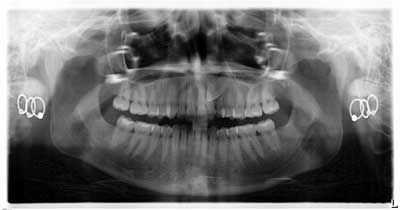

Early assessment for potential impaction is easily done by taking a panoramic radiograph at the age of 7. Ectopic positioning of canines may result in future impaction; if this is the case, then intervention can be initiated. Research has also shown that early removal of the deciduous canines can offer a favorable eruption pattern of permanent counterparts. (4,5) If crowding is present, then the arch can be expanded.

When a full permanent dentition is present (with the exception of impacted canines), the labial/palatal position of the canine will have an influence on what the provider can do. (1) Arguably, obtaining a CBCT is considered mandatory and will allow for a more inclusive treatment plan creation. If angulation is favorable, then consideration to remove the primary canine and wait six months to see if there is movement of the permanent canine is an option. If extraction of the canine(s) is needed, then a premolar substitution, which is dependent on occlusion, can be used in the space. An implant can also be an appropriate alternative. When pulling a canine into the occlusal arch, there is risk involved. Trauma to adjacent teeth (root resorption) and ankylosis are some of the most common complications.The patient was put in full orthodontics and referred to a surgeon for extraction of the primary canines, exposure, and placement of retention on the impacted canines to pull them directly down from their current position.

A ballista appliance was used to prevent a facial pull of the canines in order to avoid and prevent resorption of the roots of the lateral incisors. As movement progressed over the course of the next year, eruption of the canines was considered a success. Once in position, they will be pulled facially into occlusion.